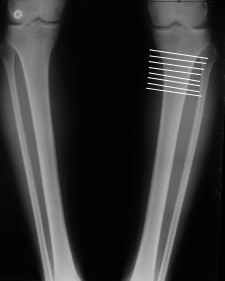

моё мнение, видимо, осталось в меньшинстве. Я остеотомию малоберцовки делаю ПРИНЦИПИАЛЬНО ВСЕГДА. Это занимает 2-3 минуты, на фоне перелома б/б кости травма ничтожная. На границе нижней и средней трети практически невозможно что-либо повредить.

4. Если внимательно посмотришь на рентгенограммы, то в зоне перелома малоберцовой кости она втягиваетсмя внутрь, таким образом немного уменьшая объем тканей по внутреннему контуру. Причем чем выше - тем эффектнее. Не надо только совсем высоко лезть - там перонеус. Многих пайциенток это тоже смущает. Так что решаем проблему комплексно. На это, кстати, особо упирает Казбек Кудзаев.

a> 4. Если внимательно посмотришь на рентгенограммы, то в зоне перелома

a> малоберцовой кости она втягиваетсмя внутрь, таким образом немного

a> уменьшая объем тканей по внутреннему контуру.

Уменьшая по внутреннему??

В общем, не рубить ее можно, когда надбугорковая остеотомия. Если делать на расстоянии 4-6 см от суставной поверхности - лучше сломать.